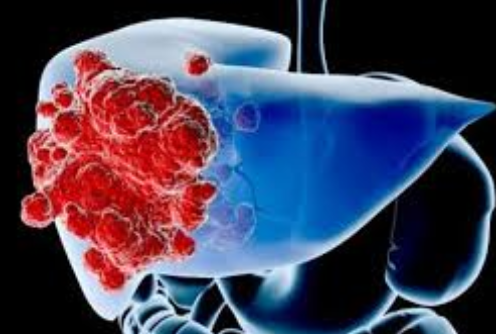

肝癌治疗在2017年之前只有多吉美一种药物,但是对于大多数国人来说,多吉美的有效率实在是太低了,而且多吉美的耐药时间太快了(中位耐药时间2.8个月)。而且多吉美耐药后,就几乎没有其他能用的治疗方案了。但是肝癌这种无药可医的情况,在2017年逐渐改善。因为有越来越多的靶向药物可用来治疗肝癌。1、瑞戈非尼:临床前研究已经证明瑞戈非尼抑制在肿瘤新生血管发生中起重要作用的几种促血管生成的VEGF受体激酶。一个三期临床数据显示:瑞戈非尼的OS:10.6个月;PFS:3.2个月;疾病控制率:65.2%;总缓解率:10.6%;总体来说治疗效果比多吉美好很多。

2、乐伐替尼:2013年开展了一项Ⅲ期临床试验(REFLECT)表明乐伐替尼在主要终点OS达到预期结果,次要终点PFS、TTP和ORR全面超越多吉美。REFLECT试验的重要临床数据:乐伐替尼的中位总生存期(OS):13.6个月;中位无进展生存期(PFS):7.4个月;客观有效率:24%。而且,据2017年CSCO的回顾性研究显示,乐伐替尼对于我国肝癌患者的治疗效果要优于欧美等国家。

3、Opdivo:Opdivo已经在2017年9月22日获得FDA批准用于多吉美治疗后进展的肝癌患者。Opdivo用于肝癌:有效率20%,控制率64%。基于一个214人的二期临床试验——Checkmate-040,缓解率14.3%,疾病控制率64%。临床数据:43名患者的肿瘤缩小至少30%,客观有效率20%,中位持续有效时间9.9个月;可使另外64名患者的肿瘤稳定不进展,疾病控制率高达64%;9个月生存率74%。除了以上靶向药物,还有卡博替尼和来那度胺可用于肝癌的治疗。